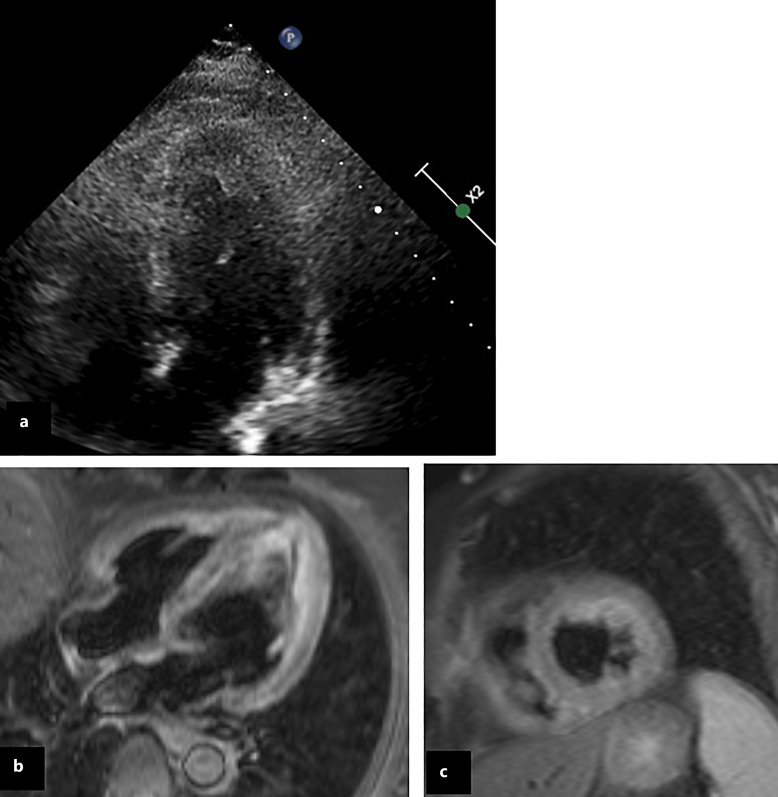

Background: Hypereosinophilic syndrome is characterized by a peripheral blood eosinophil count >1.5 × 103/μL on two different examinations within a month of each other and/or a 20% or higher percentage of eosinophils in a bone marrow section, associated with organ damage. Rarely, neurological manifestations may occur, even in the early stages. We report a case of idiopathic hypereosinophilic syndrome with Loeffler endocarditis presenting with multiple bilateral strokes and encephalopathy as the first clinical manifestations.

Summary: Hypereosinophilia and echocardiographic findings suggested a Loeffler's endocarditis. Blood hyperviscosity and small vessels inflammation induced by the hypereosinophilia itself, the embolization of intracardiac thrombus, along with the impaired clearance of microthrombi in the watershed areas, are the main mechanisms involved in the pathophysiology of stroke in the hypereosinophilic syndrome. Additionally, encephalopathy could be considered as a consequence of multiple cerebral infarcts and neurotoxicity induced by hypereosinophilia since our patient's confusion and aggressive behavior gradually remitted after steroid therapy was started.